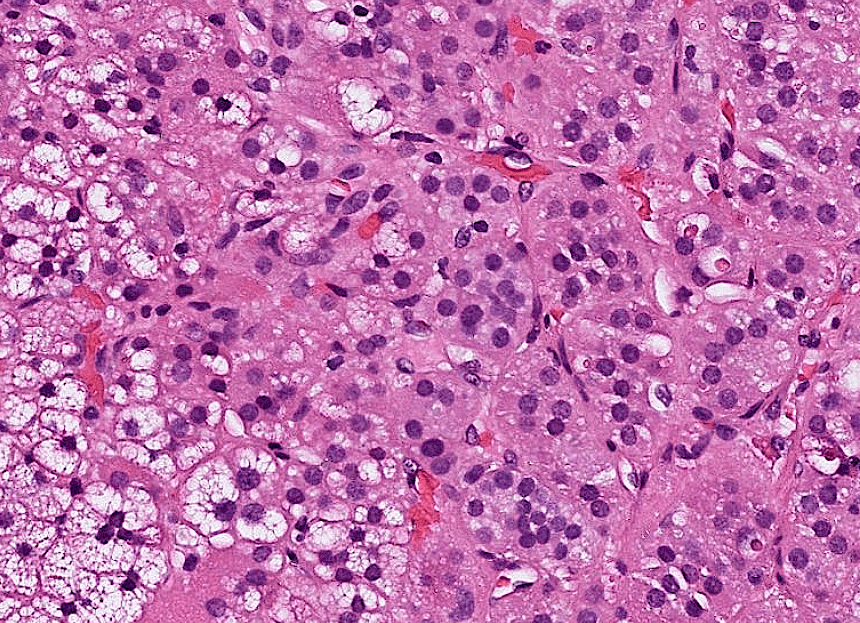

lung adenocarcinoma